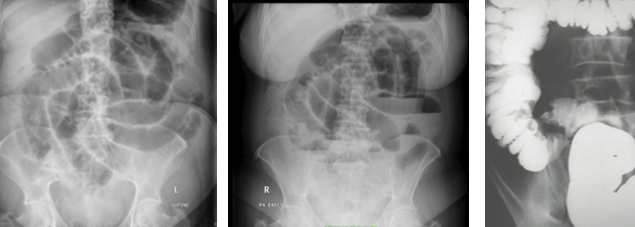

33yo patient presents with diarrhoea associated with crampy abdominal pain localised to the RLQ. Associated with this is a fever and mild arthralgia

Crohn’s disease

45yo male presents with two months of faecal frequency with loose stools, urgency and tenesmus. Associated with this is abdominal pain prior to defaecating and rectal bleeding

Ulcerative colitis